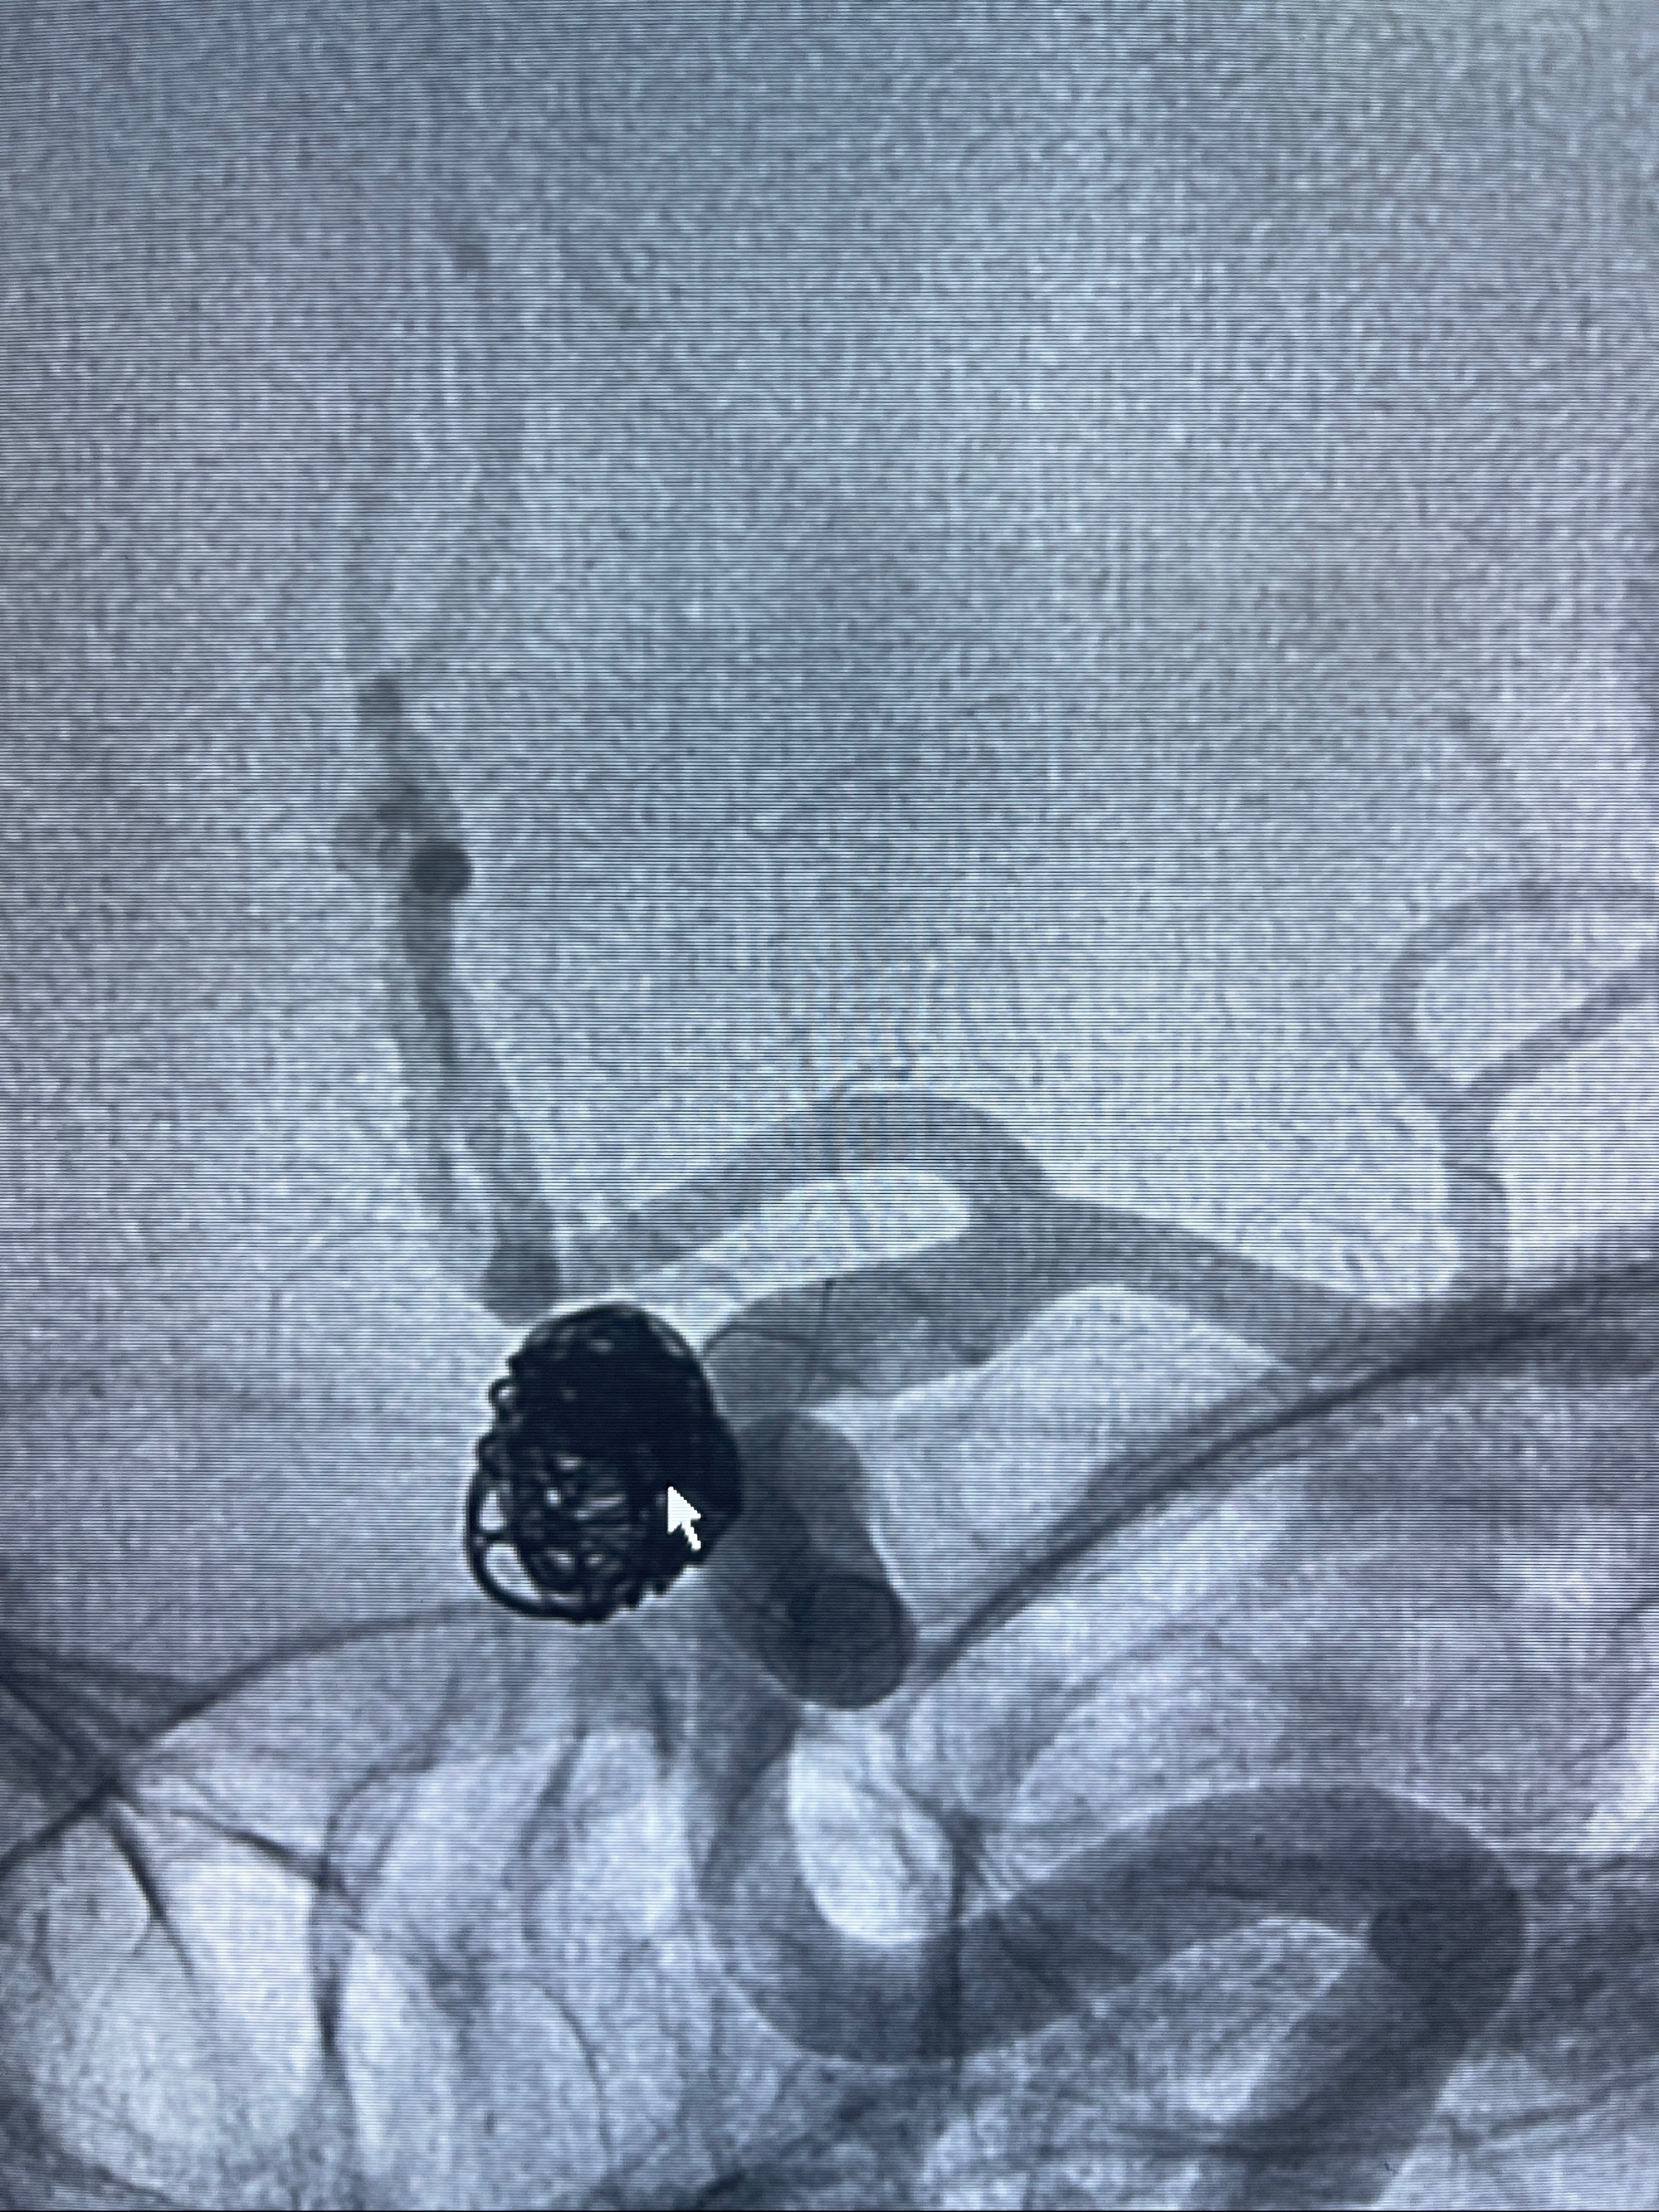

2023-08-30DSA:左侧颈内动脉眼动脉动脉瘤,约3*9.2*7.3mm大小

密网支架辅助栓塞

- Tubridge 4.0-20mm密网支架

- 加奇微弹簧圈:7*30/6*20/5*20/2*8

术后3D显示支架贴壁佳